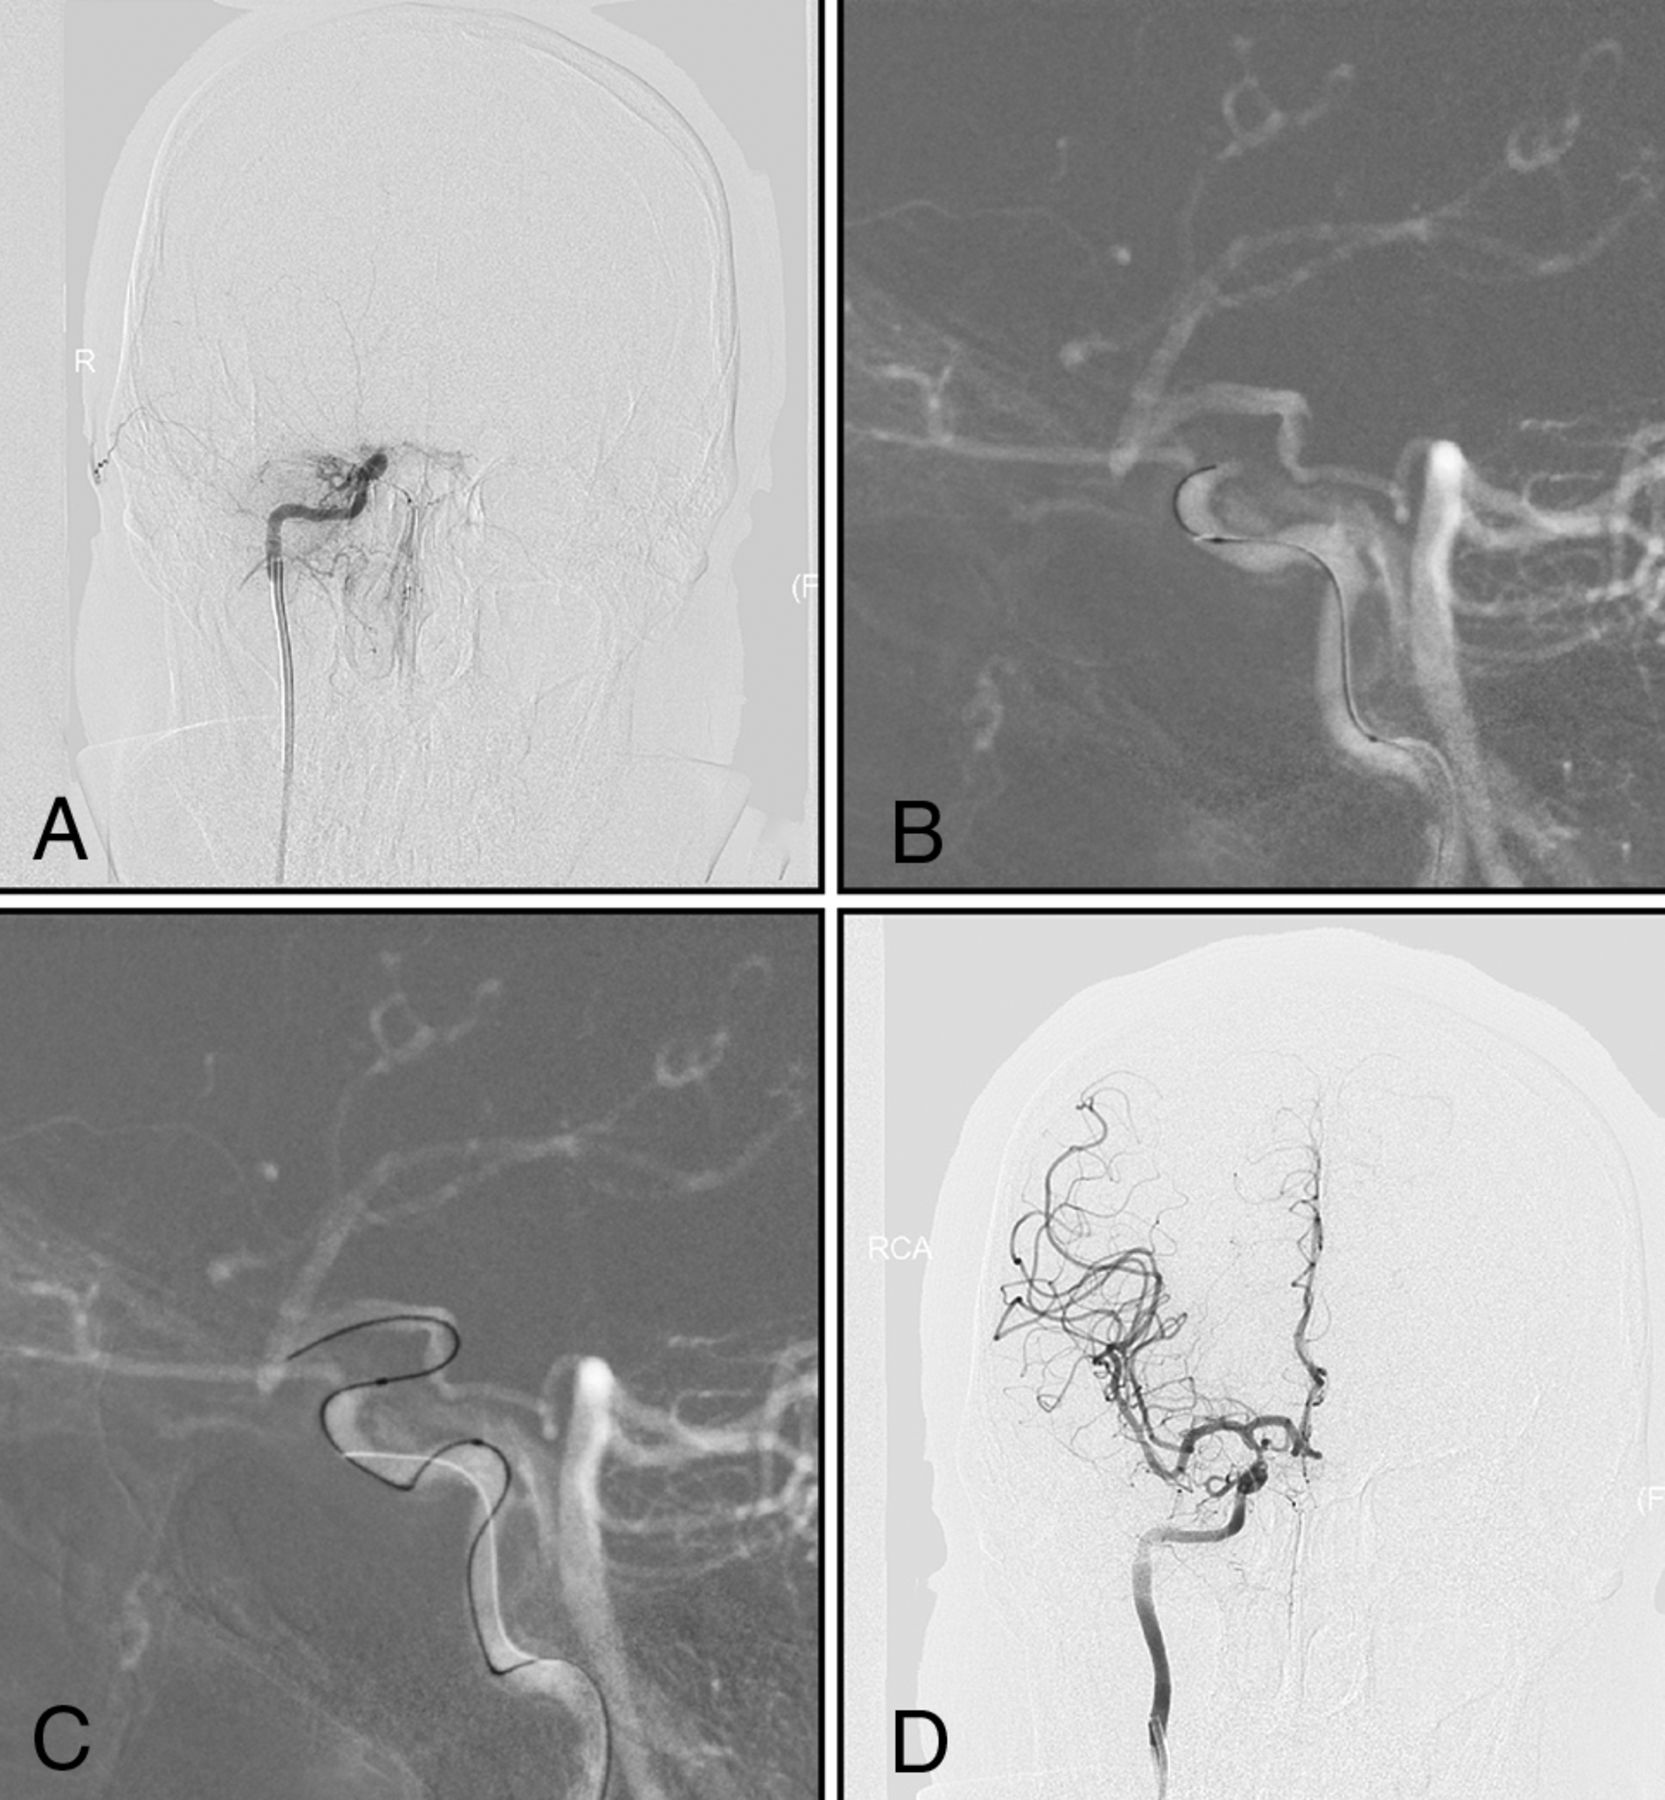

A man with left-sided weakness for 15 days. A, DSA shows that the right intracranial internal carotid artery is occluded, with an occlusion length of ≤10 mm and established collateral filling to the distal intracranial ICA via the PcomA (type I). B and C, Under dual-roadmap guidance, the microwire in combination with a microcatheter passes through the occluded segment. D, Successful recanalization.